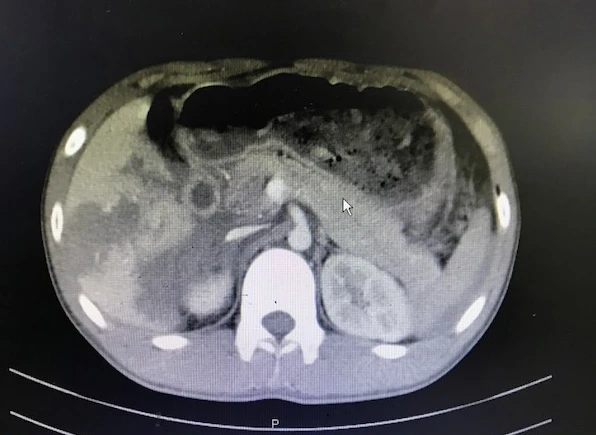

Các bác sĩ (BS) chẩn đoán và ghi nhận bệnh nhân có dịch ổ bụng lượng nhiều nên tiến hành giảm đau và bù dịch. Chưa hết, kết quả chụp CT scanner toàn thân cho thấy bệnh nhân vỡ gan phải độ 3-4, dập tá tràng và đầu tụy, tụ máu sau phúc mạc gây xuất huyết ổ bụng.

Kết quả chụp CT scan cho thấy bệnh nhân bị dập tá tràng và đầu tụy. Ảnh: VÕ CHI